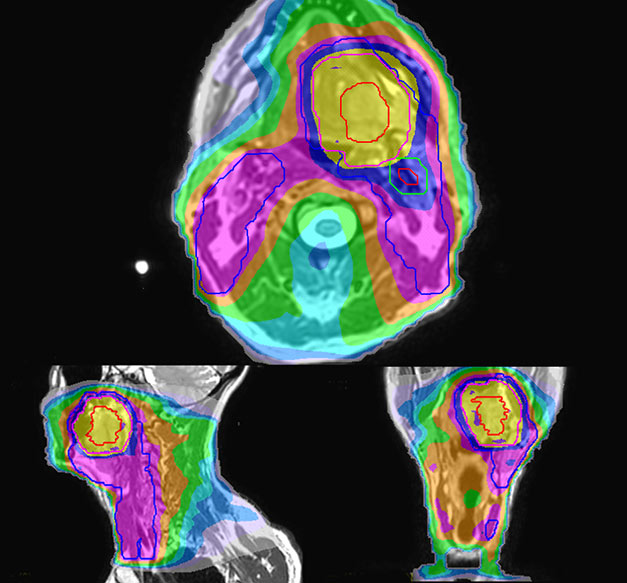

Epidermoid carcinoma of the left tongue base

The patient was diagnosed with an epidermoid carcinoma of the base of the left invading the amygdala lodge and the amygdaloglossal groove. Radiochemotherapy with curative aim was prescribed with a dose of 70 Gy for the tumor, 66 Gy on the suspicious nodes and 56 Gy on the elective drainage areas - in 33 fractions.

T2W 3D, 3D STIR and mDIXON MRI scans.

MR-based target contouring on 3D T2W TSE in transversal, sagittal and coronal planes.

Personalized VMAT dose planned in Philips Pinnacle.